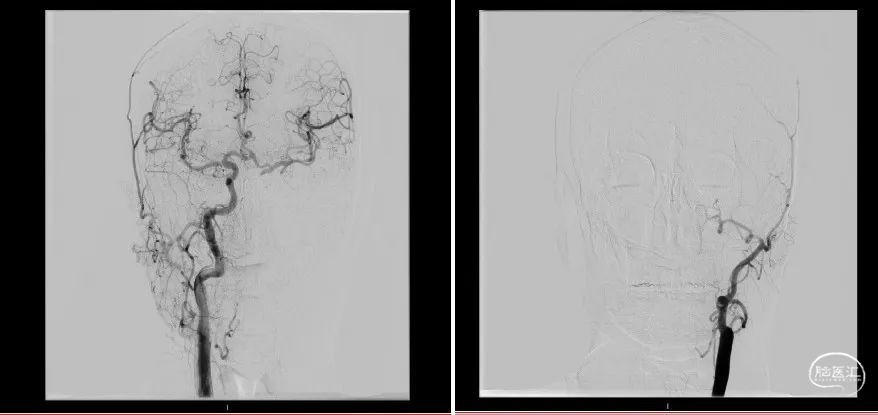

复查造影:下干完全再通。

静待15分钟后再次复查造影,见患者血管通畅,前向血流良好,mTICI 3级。大脑前动脉、前交通动脉血流通畅,对侧M1显影良好,术中患者生命体征平稳,术毕。

2022.5.12复查造影